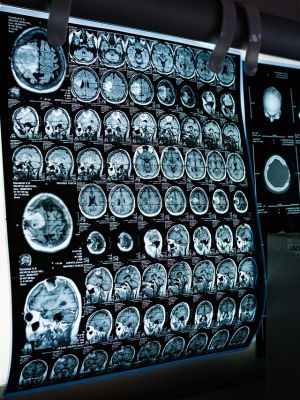

U Balkan Medici možete obaviti najjeftiniju i najbolju magnetnu rezonancu glave uz dostupne popuste i akcije. Cena magnetne rezonance uključuje pregled i tumačenje nalaza. Nakon snimanja, radiolog interpretira slike, a rezultati su dostupni u elektronskoj formi. Magnetna rezonanca je korisna za dijagnostiku neurologskih stanja i praćenje poznatih oboljenja.

Magnetna rezonanca glave predstavlja savremenu dijagnostičku metodu koja omogućava prikaz unutrašnjih struktura mozga i lobanje koristeći snažno magnetno polje i radio-talase. Ova metoda je posebno korisna za detekciju promena u mozgu koje su nevidljive ili teško uočljive drugim metodama snimanja.

Magnetna rezonanca omogućava lekarima da steknu detaljan uvid u stanje mozga bez potrebe za operacijom. Snimci koje pruža su izuzetno jasni i mogu otkriti i najmanje promene koje su važne za pravilnu dijagnozu.